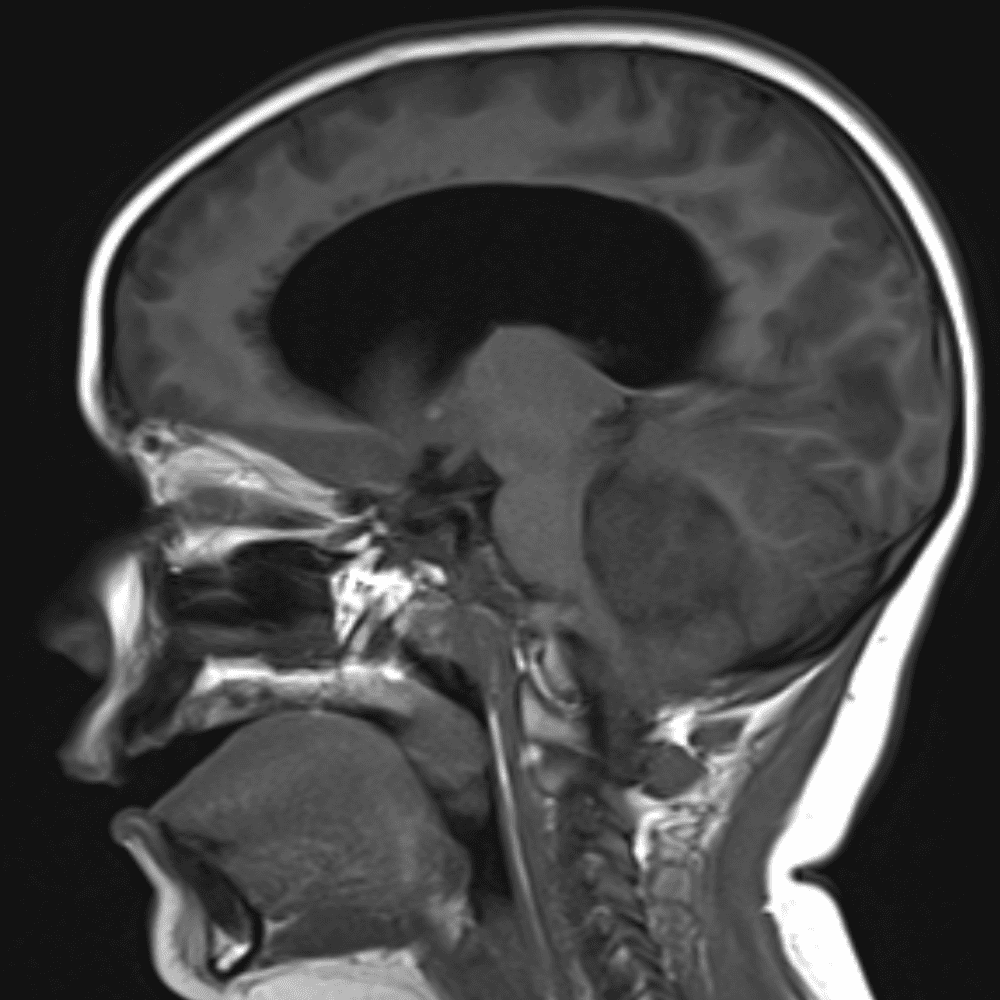

Classic Cases